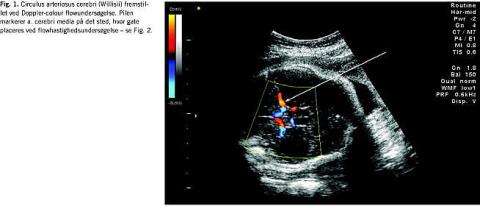

I graviditeter med anæmirisiko for fosteret ønskes viden om fosterets hæmoglobinkoncentration (Hb) som næste trin i udredningen. Niveauet er afgørende for om transfusionsbehandling skal iværksættes eller om igangsættelse af fødslen bør tilrådes, hvis gestationsalderen er fremskreden. Mange metoder har været forsøgt for at opnå denne viden, uden at være nødsaget til at foretage cordocentese med de dertil hørende risici. Antistofniveauet i maters blod giver over en vis cut-off- værdi en dårlig prædiktion af foster-Hb. Hydrops/ascites hos fosteret er meget let at se ved ultralydskanning, men problemet med dette sygdomstegn er, at det forekommer sent i anæmiudviklingen, og at ikke alle fostre udvikler hydrops selv ved meget lav Hb. Endvidere at resultaterne ved behandling af fostre, der allerede er hydrope, når behandling påbegyndes, er klart dårligere end for non-hydrope [3]. Gennem mange år anvendtes monitorering ved at foretage gentagne amniocenteser i løbet af graviditeten med bestemmelse af amnionbilirubin. Værdierne plottedes på et Liley chart, hvor fosterets sandsynlighed/risiko for at blive født med henholdsvis svær anæmi, moderat anæmi eller normal Hb kunne aflæses. Da denne metode er invasiv og ikke så præcis, har mange kliniske forskere forsøgt at finde bedre noninvasive metoder. Bl.a. har følgende været evalueret: miltomkreds, leverlængde, diameter af v. umbilicalis, placentatykkelse og flow indices ved Doppler-undersøgelse af mange forskellige føtale kar [4]. Et gennembrud kom, da man begyndte at måle de maksimale systoliske flowhastigheder (PSV) i a. cerebri media (MCA) (Fig. 1 og Fig. 2 ). Mari et al [5] publicerede i 2000 et multicenterstudie med PSV-MCA og føtal-Hb fra 111 gravide med immunisering og 265 kontroller. Ved retrospektiv analyse fandtes at ved en PSV cut-off -værdi på 1,5 multiplikationer af medianværdien (MOM) og en Hb-cut-off -værdi for transfusionskrævende anæmi på 0,65 MOM fandtes en sensitivitet på 100% og falsk positivrate på 12%. I senere studier med evaluering af MCA-Doppler er der fundet sensitivitet på 88-96% og specificitet på 71-100% [6-8]. Efter 35. uge findes dog en meget høj falsk positivrate [6]. Kontrol med amnionbilirubinbestemmelse er ved mange centre nu erstattet af ultralydkontrol med måling af MCA-PSV.